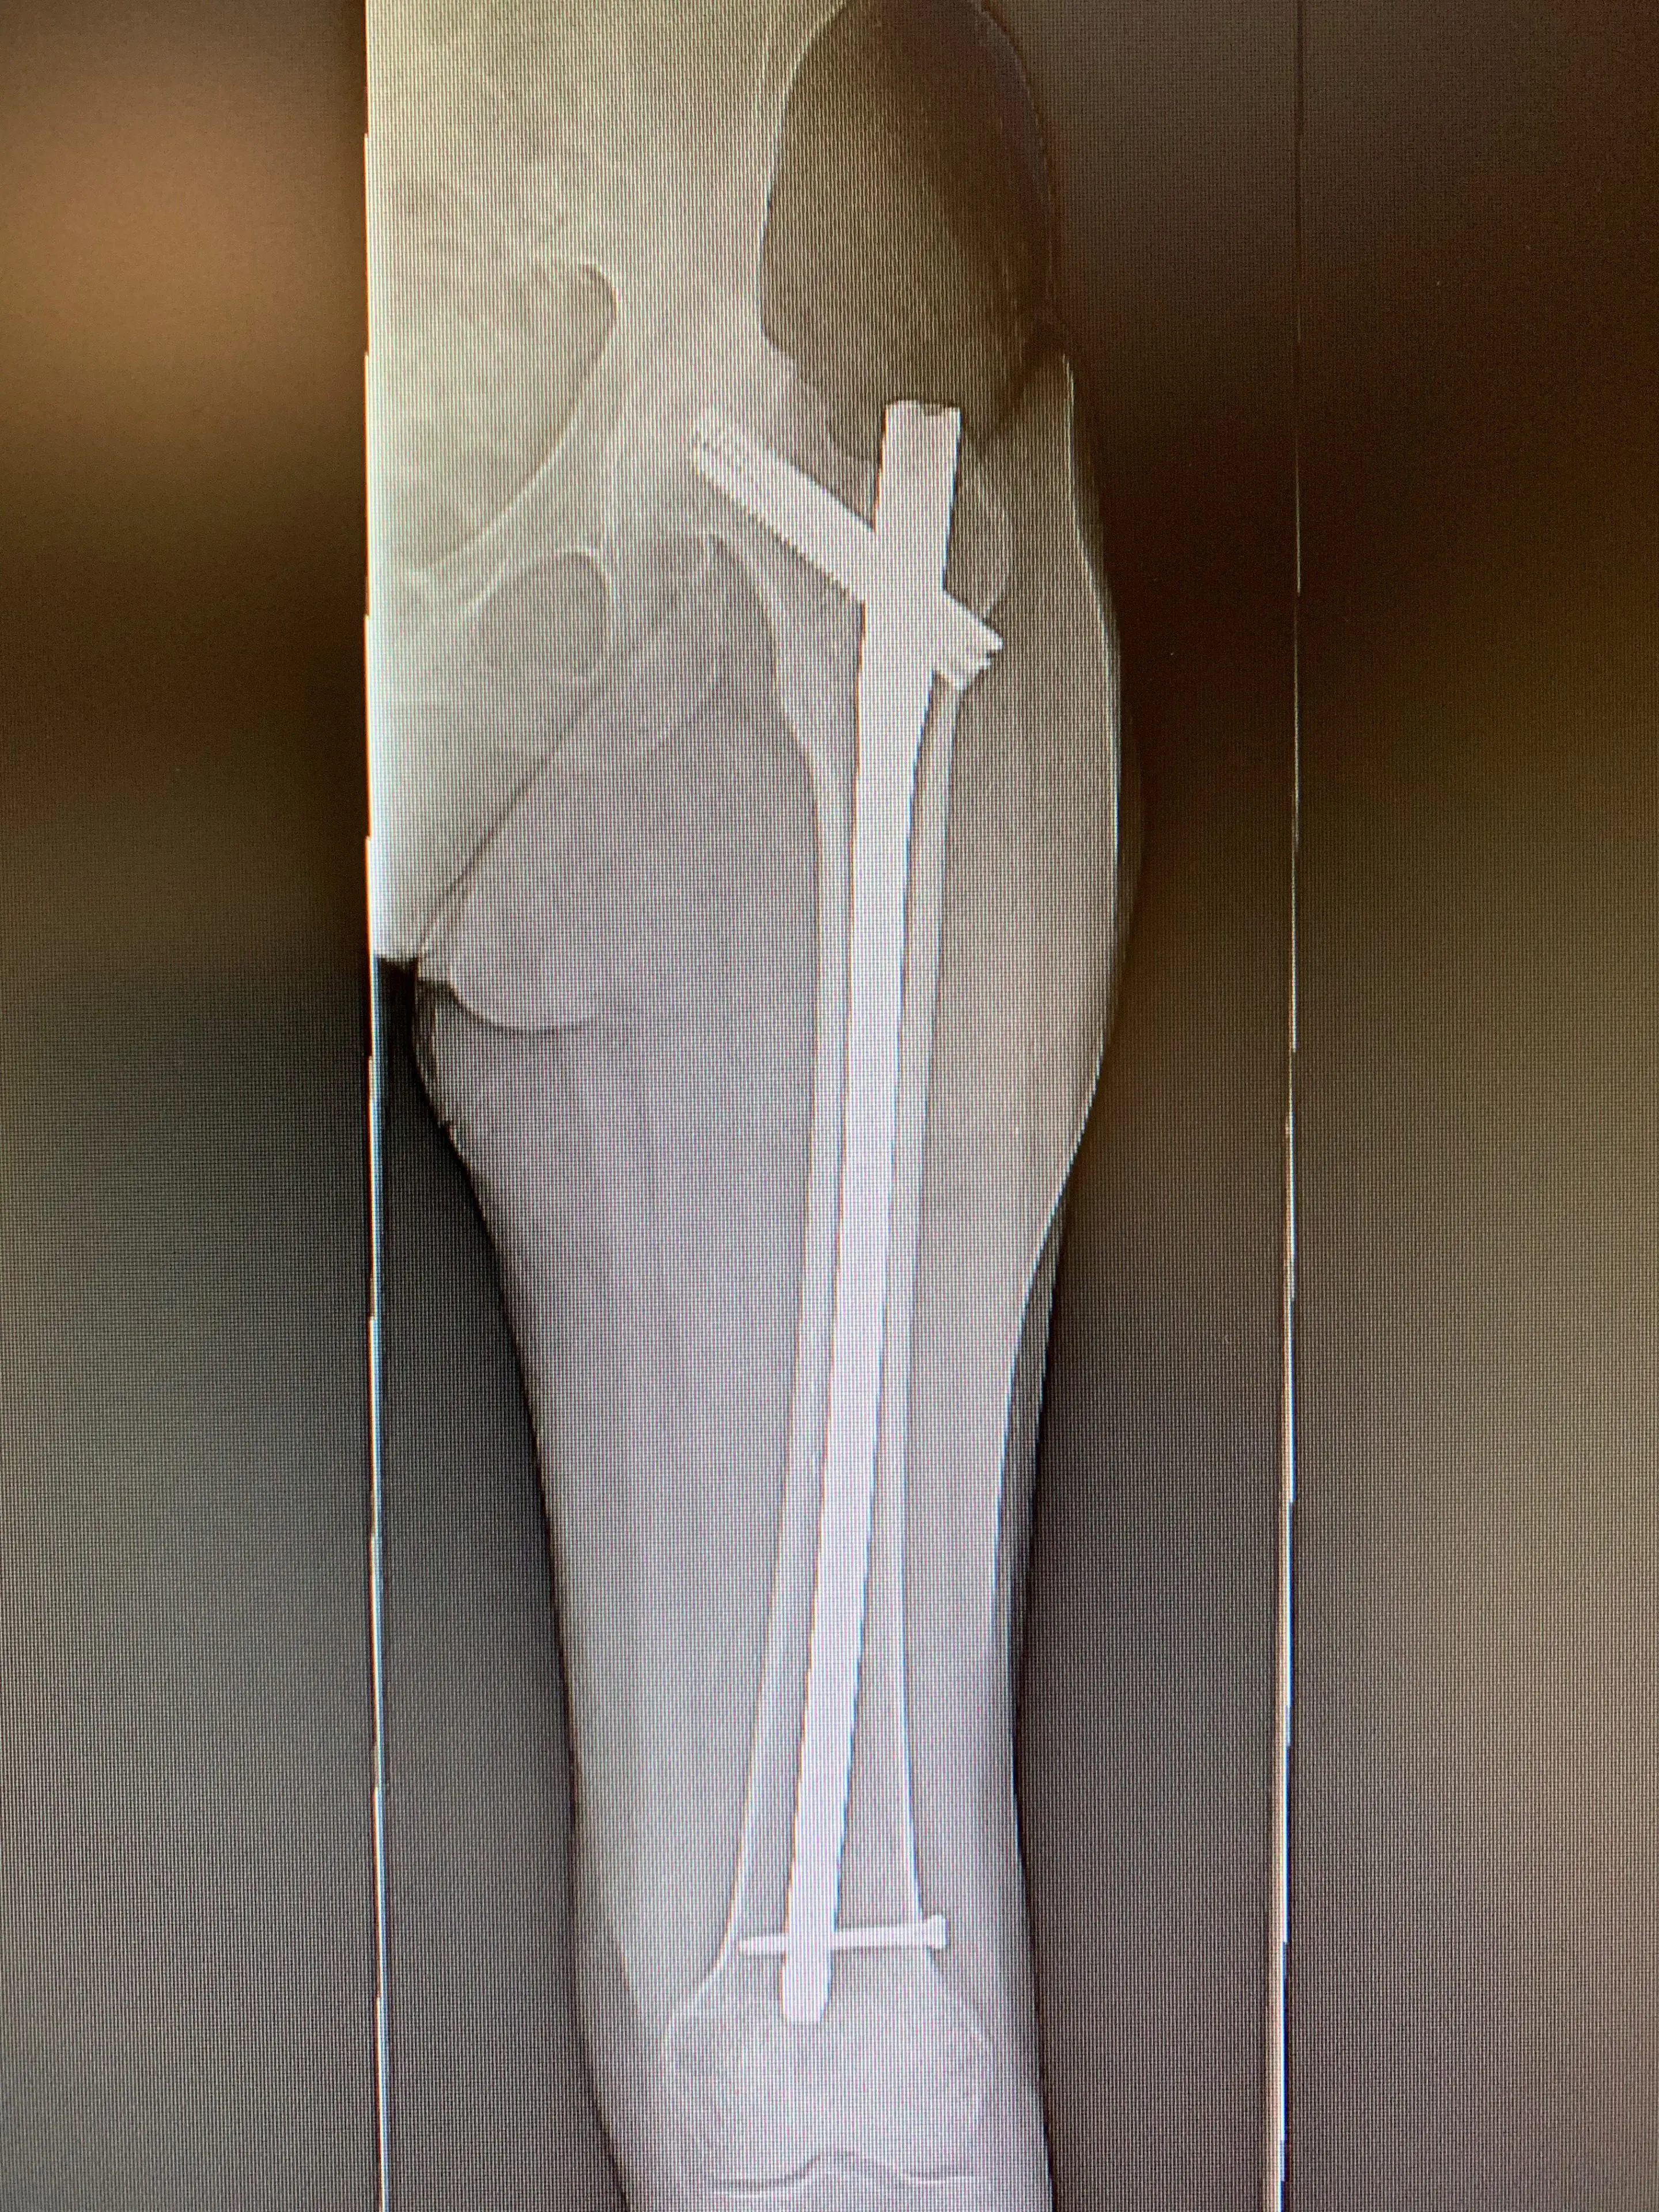

During her surgery, we first identified the insertion sites of the various components of her femur fracture hardware, and removed these carefully in the appropriate sequence. Once they were fully removed, we then began the hip replacement part of the procedure. Her acetabular component was placed without event, her femoral component proved more challenging to prepare for, given the new bone her body had formed in the area of the fracture. With careful removal of the bone blocking the femoral canal, we managed to implant a special femoral component that bypassed the site of the fracture, significantly reducing the risk of her femur fracturing again in the same area.

Post-op